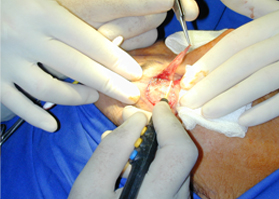

對軟組織切口的比較